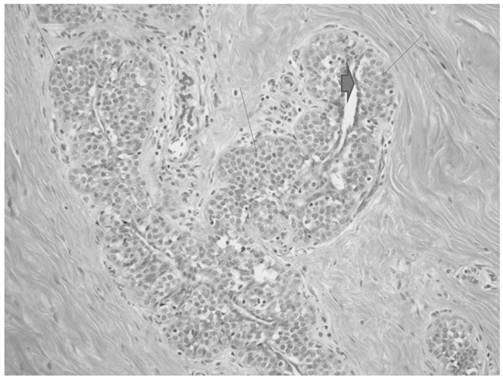

The breast reduction specimen consisted of 426 grams of tissue from the right breast and 490 grams of tissue from the left breast. Gross examination revealed 80% fibrous tissue and 20% adipose tissue without a discrete mass. Extensive histopathologic sampling of the left breast revealed a few foci of lobular carcinoma in situ which was confirmed with a negative E-cadherin immunostain (Figures 4 and 5). Atypical duct cell hyperplasia, cribriform and micropapillary type was also present in a few foci on the left (Figure 6). Both right and left breasts revealed gynecomastia, florid phase.

Figure 4

Monotonous small cells of lobular carcinoma in situ (thin arrows) show pagetoid extension along ducts with undermining of normal ductal epithelium (thick arrow).

Figure 5

E-cadherin immunostain shows absence of staining in cells of lobular carcinoma in situ (thin arrows) with positive staining in residual benign ductal cells (thick arrow).